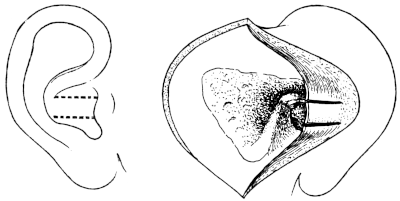

| 315. | Incisions for Lateral Rhinotomy (Moure’s Operation) | 619 |

| 316. | The Area of Bone removed in Lateral Rhinotomy | 619 |

| 317. | Lateral Rhinotomy | 620 |